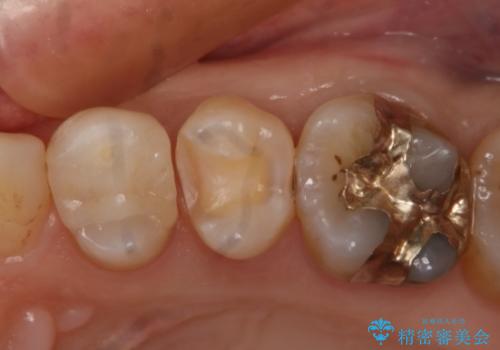

- 左上奥歯の銀歯のやり変えを希望された患者様です。

白くしたいとの事だったので形態・切削量を考慮し、セラミックインレーでの治療を計画しました。